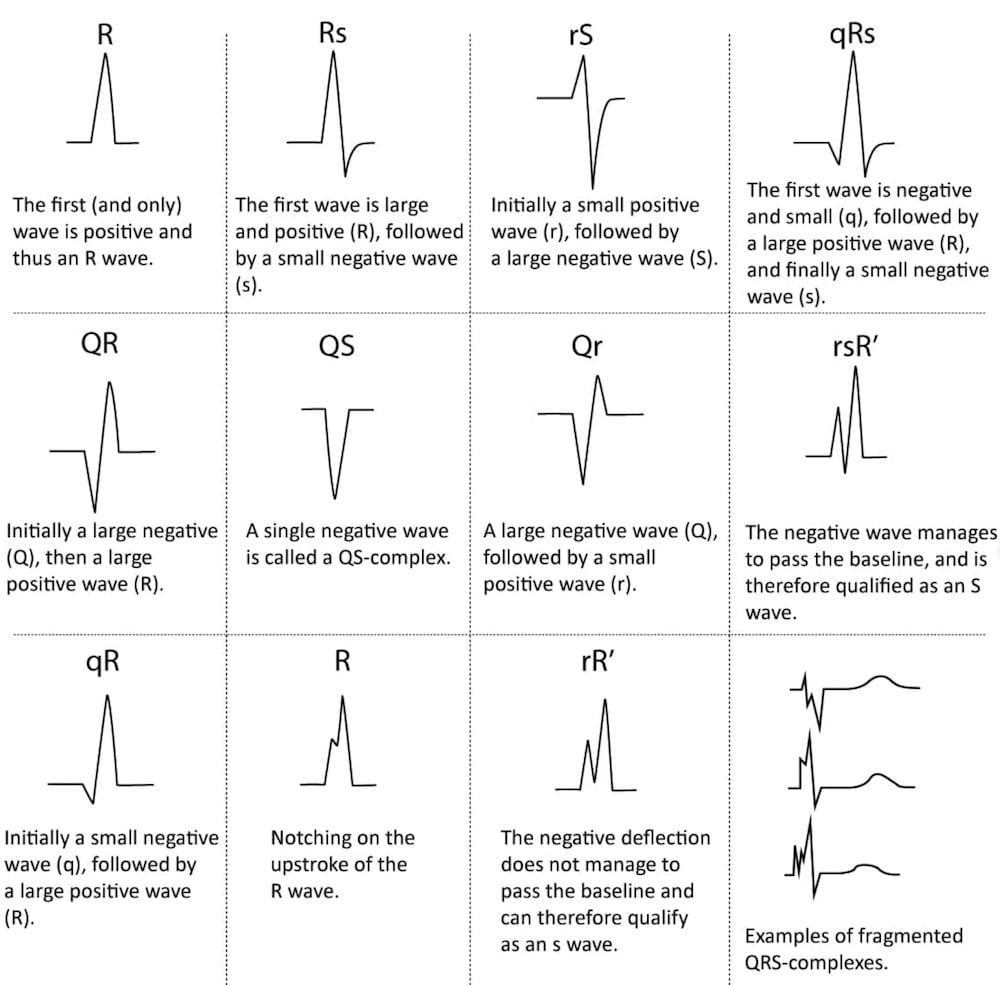

QRS Interval LITFL ECG Library Basics

https://litfl.com/wp-content/uploads/2018/10/Naming-of-the-QRS-complex-ECGWAVES.jpg

QRS Interval LITFL ECG Library Basics